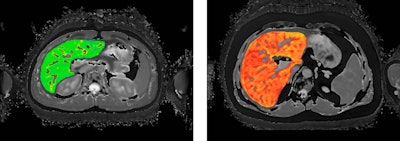

LiverMultiScan provides reports from quantitative multiparametric liver MR scans to help clinicians diagnose and manage fatty liver disease, including nonalcoholic steatohepatitis (NASH). The RSNA, American College of Radiology, and other prominent U.S. radiology associations submitted the CPT codes to the AMA CPT editorial panel.